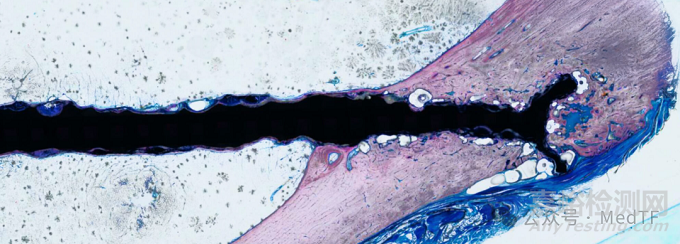

Bioretec宣布其基于鎂合金技術的可生物降解RemeOs DrillPin獲FDA授予的"突破性設備認定"。RemeOs DrillPin適用于用于兒童及成人患者的骨折塊固定,以及用于治療年齡≥2歲且具有開放性生長板的兒童患者的干骺端骨折,包括臨床上需要跨生長板固定的經骺線適應癥。

Bioretec是一家創(chuàng)新醫(yī)療器械公司,致力于通過完全可生物降解的植入物技術引領骨科護理變革。Bioretec在活性植入物的生物界面領域建立了獨特能力,旨在增強骨生長并加速骨科手術后的骨折愈合。